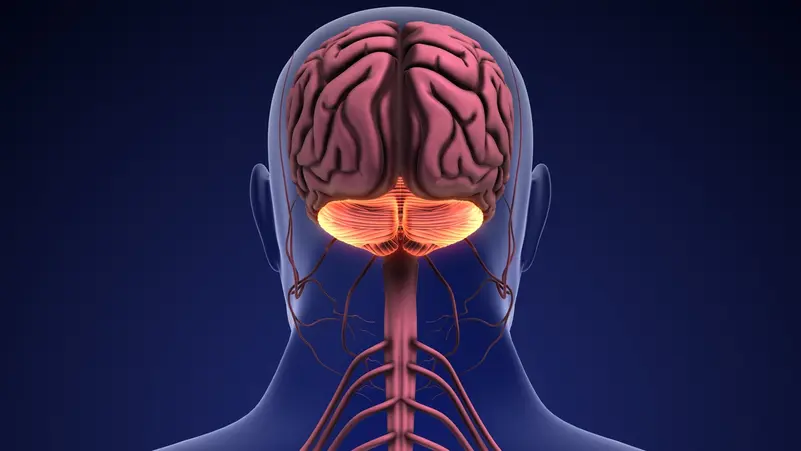

لطالما اعتُبر المخيخ – أو ما يُعرف بـ”الدماغ الصغير” – مركزاً مسؤولاً أساساً عن التوازن وتنسيق الحركة والتحكم في الاستجابات الحركية. غير أن دراسة علمية جديدة استندت إلى تحليل صور دماغية جُمعت على مدى 16 عاماً، تكشف أن هذا الجزء من الدماغ يؤدي دوراً أعمق وأكثر تخصصاً في معالجة اللغة البشرية مما كان يُعتقد سابقاً.

وأظهر الباحثون أن أربع مناطق محددة في الجزء الخلفي الأيمن من المخيخ تنشط باستمرار عند قراءة اللغة أو الاستماع إليها. والأكثر إثارة أن واحدة من هذه المناطق، التي أطلق عليها اسم LangCereb3، بدت متخصصة في اللغة بشكل شبه حصري، إذ استجابت للمهام اللغوية فقط، دون أن تنشط عند أداء مهام معرفية أخرى مثل حل المسائل الرياضية أو الاستماع إلى الموسيقى.

ويشير الباحثون إلى أن هذا الاكتشاف يُعد دليلاً قوياً على أن المخيخ ليس مجرد “مساعد حركي”، بل عنصرا فاعلا في الشبكة العصبية المسؤولة عن فهم اللغة وإنتاجها.

ورغم أن المخيخ لا يشكّل سوى نحو 10% من حجم الدماغ، فإنه يحتوي على ما يقرب من 80% من مجموع الخلايا العصبية فيه، ما يمنحه قدرة هائلة على معالجة المعلومات. وقد دفعت هذه الحقيقة العلماء، خلال السنوات الأخيرة، إلى إعادة النظر في دوره في وظائف معرفية عليا، مثل التفكير، والانتباه، واللغة.

وتُعيد هذه النتائج رسم خريطة اللغة في الدماغ البشري، وتؤكد أن معالجة اللغة ليست محصورة في القشرة الدماغية وحدها، بل تعتمد على شبكة أوسع وأكثر تعقيداً تشمل المخيخ. ويخلص الباحثون إلى أن فهم الدور الدقيق لهذا “الدماغ الصغير” قد لا يساعد فقط في تفسير كيفية تطور اللغة لدى الإنسان، بل قد يشكّل خطوة حاسمة نحو تحسين علاج الاضطرابات اللغوية واستعادة القدرة على التواصل لدى ملايين المرضى حول العالم.